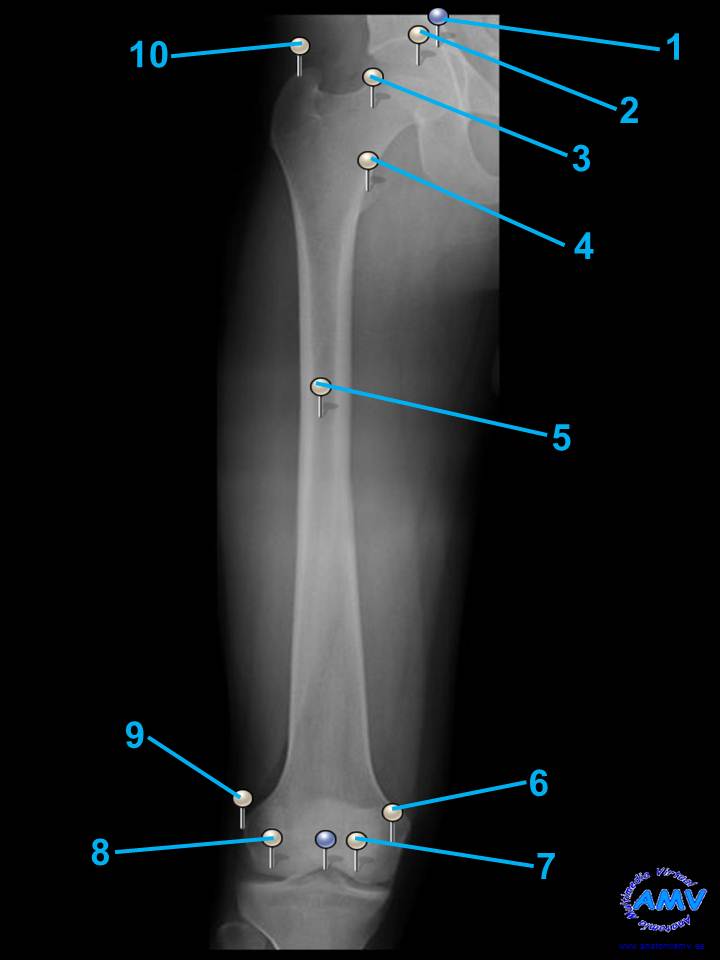

Radiografía del Muslo

rx_mi_04.jpgIndique que estructura se señala con el número correspondiente:

El nº 1 señala .

El nº 2 señala .

El nº 3 señala .

El nº 4 señala .

El nº 5 señala .

El nº 6 señala .

El nº 7 señala .

El nº 8 señala .

El nº 9 señala .

El nº 10 señala .